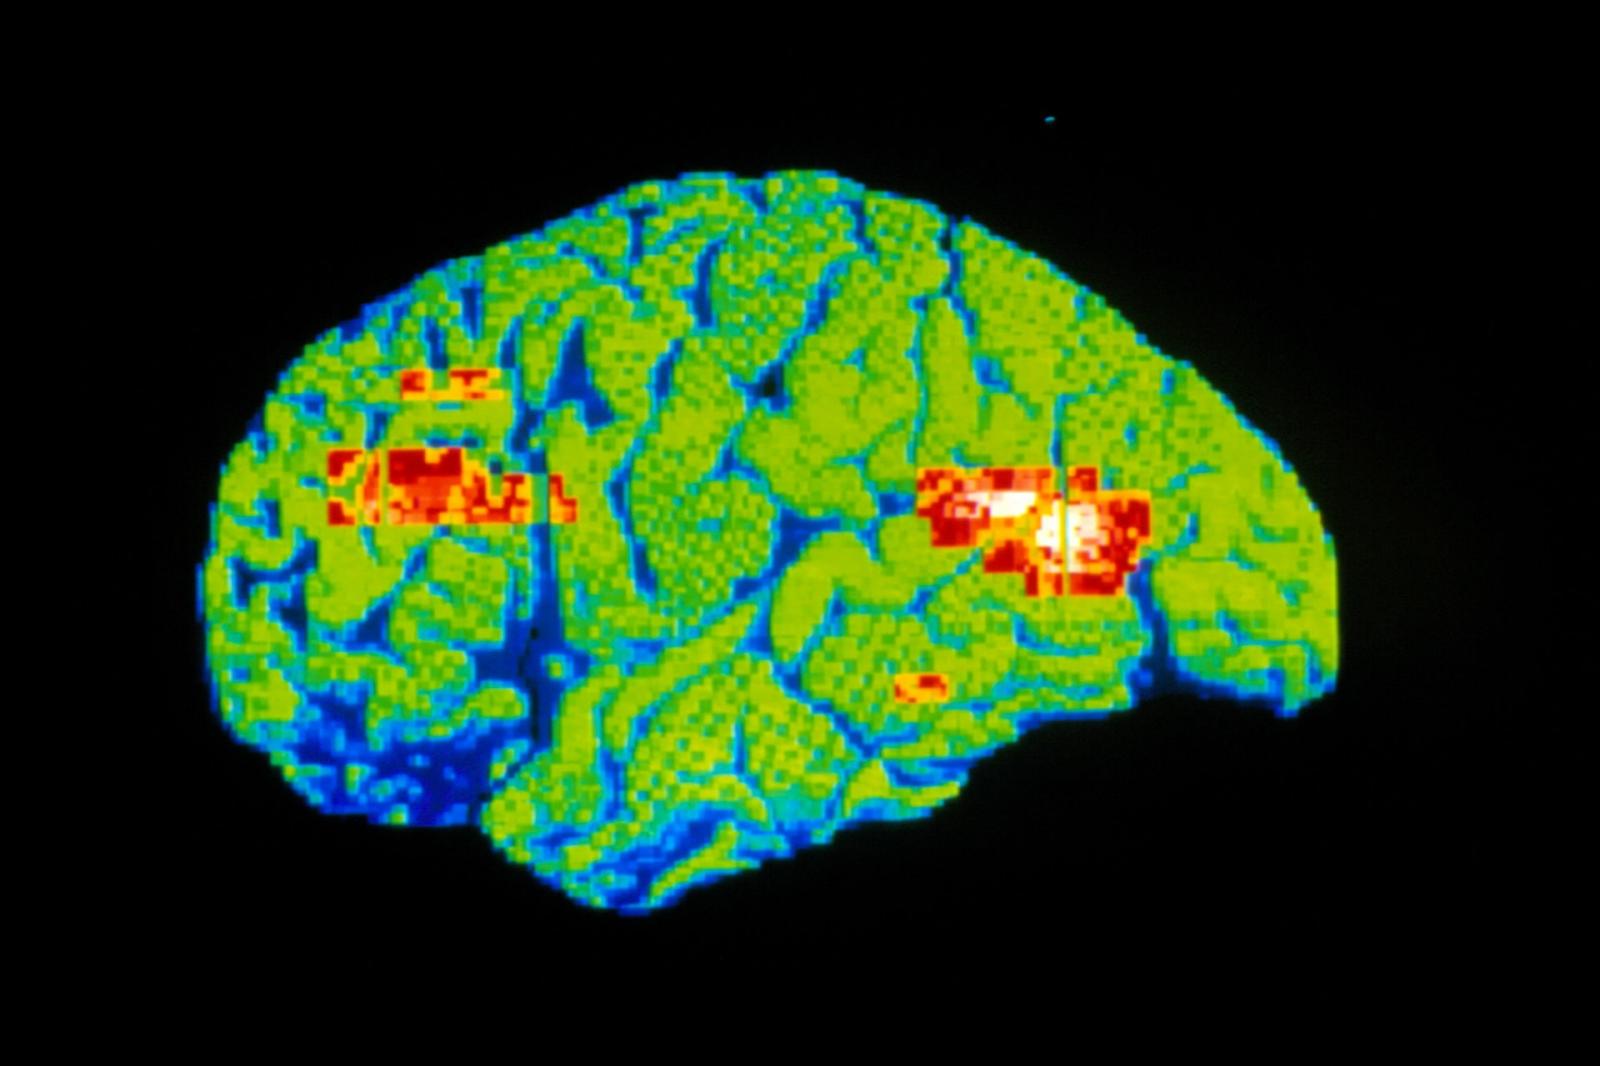

Na década de 1990, o interesse voltou-se para o potencial da droga para combater a depressão, quando um cientista do governo chamado Phil Skolnick argumentou que o direcionamento dos caminhos do glutamato - os principais processos "excitatórios" ou neuroativadores do cérebro - poderia produzir efeitos antidepressivos. Em 2000, uma equipe de pesquisadores da Universidade de Yale e do Centro de Saúde Mental de Connecticut, liderados pelo Dr. Robert M. Berman, relataram que doses de cetamina proporcionavam alívio rápido a sete pessoas com depressão.

O campo decolou em 2006, quando uma equipe do Instituto Nacional de Saúde Mental, liderada pelo Dr. Carlos Zarate Jr., relatou que 18 pessoas resistentes ao tratamento que receberam a droga por via intravenosa relataram que seu desespero se dissipou em questão de horas.

"O que parece notável é que a droga também parece ajudar outros domínios além da depressão, como ansiedade, pensamento suicida e anedonia" - a incapacidade de sentir prazer - disse o Dr. Zarate, chefe do ramo de terapêutica experimental e fisiopatologia do NIMH. "Parece ter efeitos mais amplos, em muitas áreas de humor."